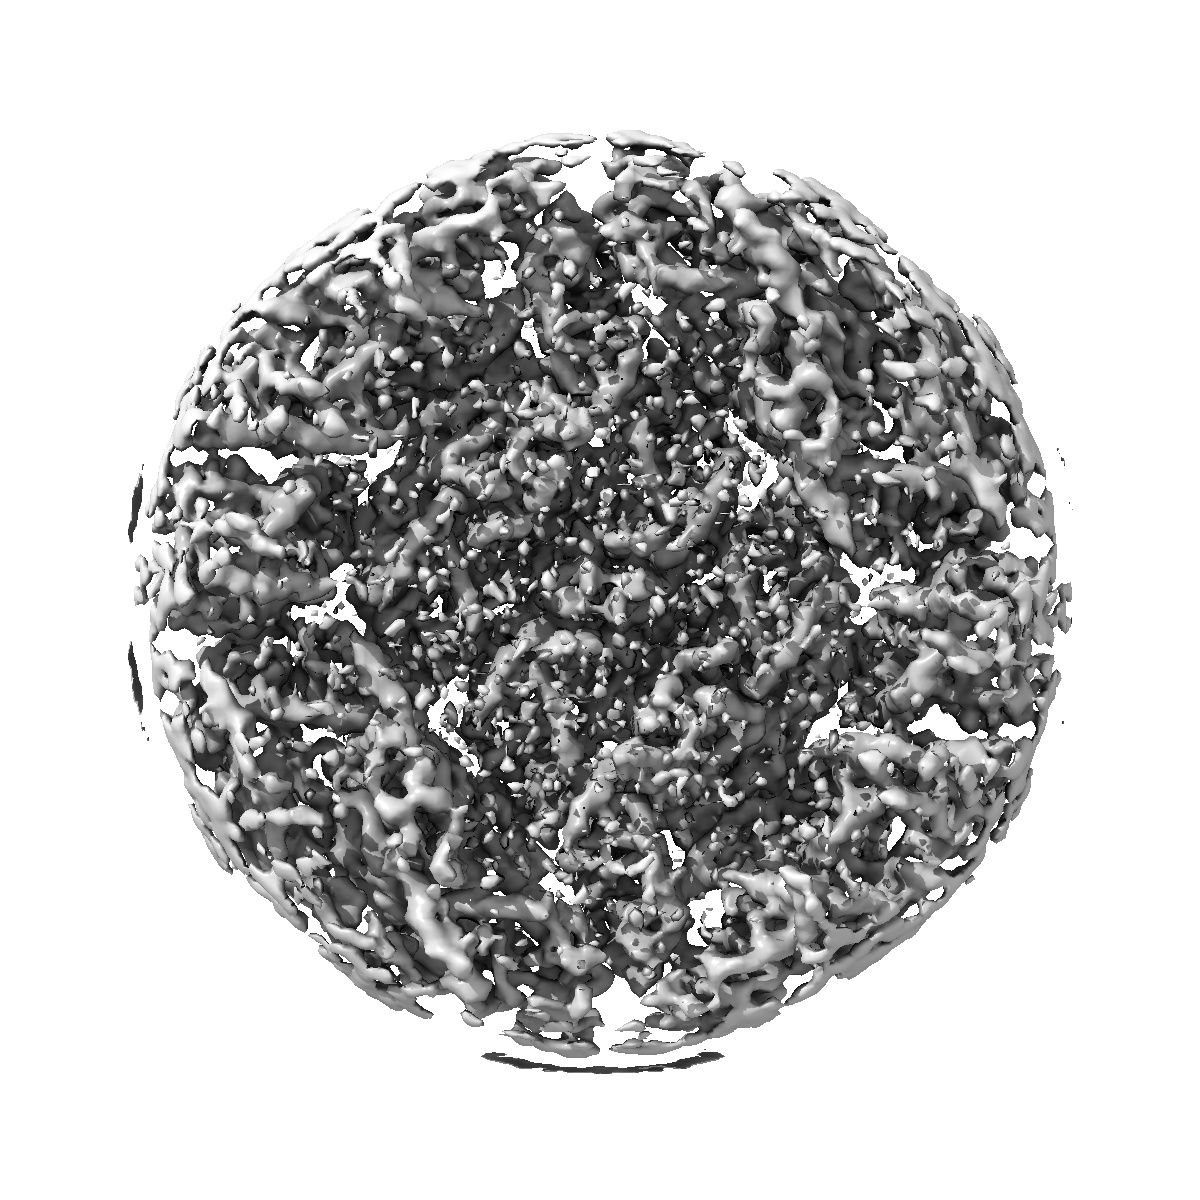

Cryo-EM structure of dengue virus serotype 3 strain 863DK in complex with human antibody DENV-115 Fab at 37 deg C (subparticle LLR-LRR)

Single-particle5.4 Å

Sample: Dengue virus serotype 3 strain 863DK in complex with human antibody DENV-115 Fab at 37 deg C